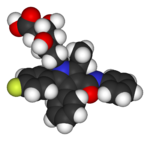

Several important pharmaceuticals contain fluorine. Of commercialized drugs, already 20% contain fluorine, as even a single atom of it improves the chemical reactivity of the drug molecule used.

Because of the considerable stability of the carbon-fluorine bond, many drugs are fluorinated to delay their metabolism (turning into another molecule; the chemical process behind this is how the drugs work). This prolongs their half-lives and allows for longer times between dosing and activation. For example, an aromatic ring may add to prevent the metabolism of a drug, but this presents a safety problem, because some aromatic compounds are metabolized in the body into poisonous epoxides by the organism's native enzymes. Substituting a fluorine into a para position, however, protects the aromatic ring and prevents the epoxide from being produced.

Adding fluorine to biologically active organics increases their lipophilicity (ability to dissolve in fats), because the carbon–fluorine bond is even more hydrophobic than the carbon–hydrogen bond. This effect often increases a drug's bioavailability because of increased cell membrane penetration. Although the potential of the fluorine to be released as a fluoride leaving group depends on its position in the molecule, organofluorides are generally very stable, since the carbon–fluorine bond is strong.

Many SSRI antidepressants are fluorinated organics, including citalopram, escitalopram, and fluoxetine. Fluoroquinolones are a commonly used family of broad-spectrum antibiotics.

|

| Lipitor (atorvastatin) | 5-FU (fluorouracil) | Florinef (fludrocortisone) | Isoflurane |